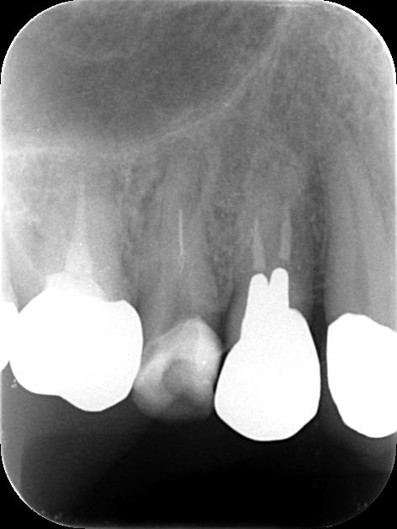

ファイル除去前 ![]() |

レントゲンで確認すると、ファイルが破折している可能性が確認できました。 |

精密検査の結果、折れた器具の見える位置にありますのでマイクロスコープを使い、自費診療の器具を用いれば除去できる可能性があります。 |